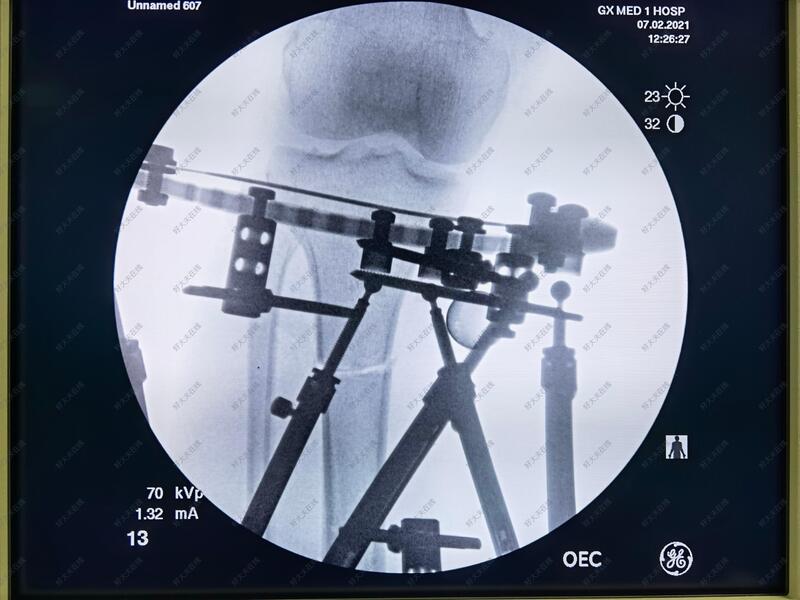

治疗中

六轴空间矫形支架具有调节精准准,病人可以早期负重